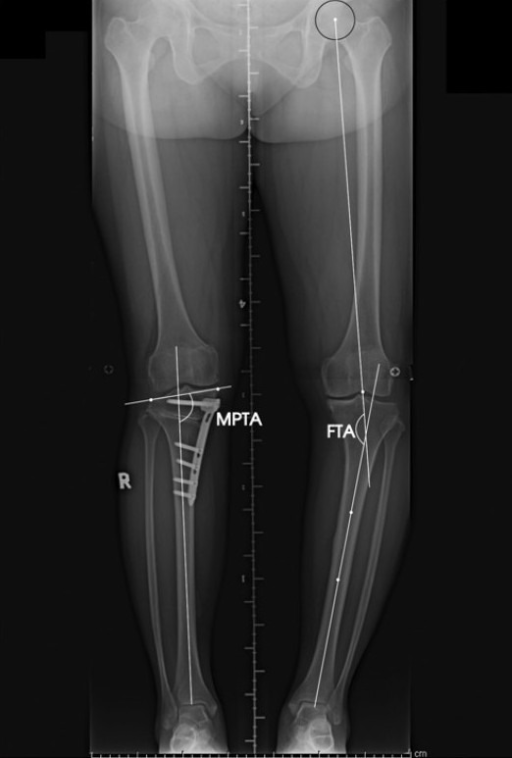

Ángulo femorotibial / Femorotibial angle

Femorotibial angle*

A description of the angular relationship between the femur and tibia at the knee expressed as varus or valgus alignment. It is measured on weight-bearing radiographs of the entire lower extremity or is clinically estimated while the subject is standing.

*O «ángulo del genu valgum». *Also «femoral-tibial angle» (FTA).